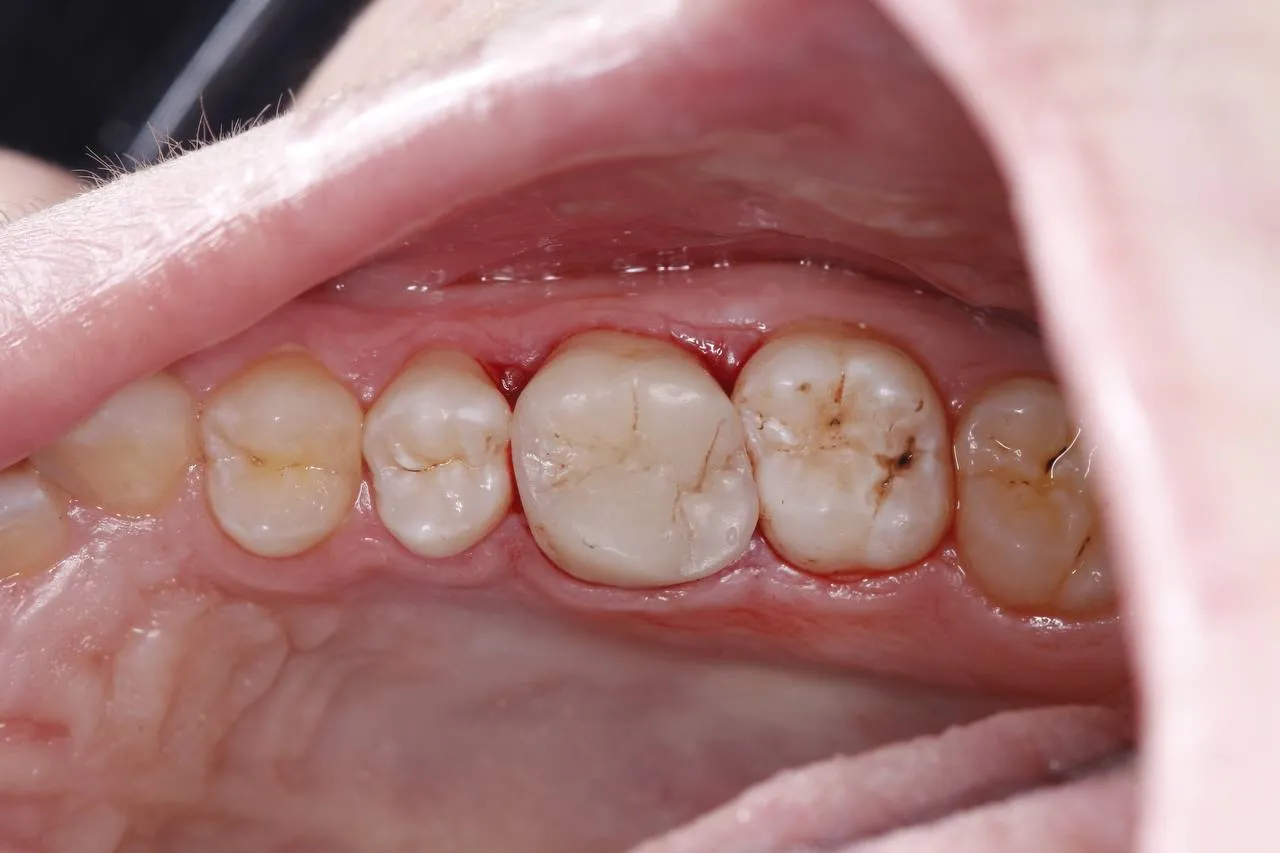

Лікування карієсу під мікроскопом зуба 16